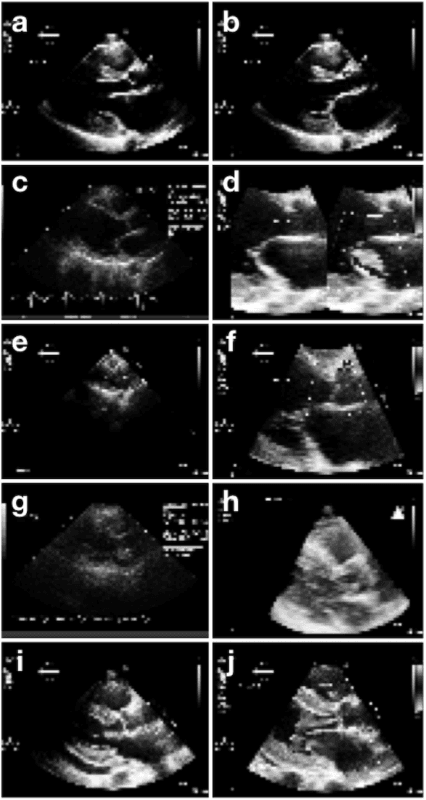

Abstract:Echocardiography is essential to modern cardiology. However, human interpretation limits high throughput analysis, limiting echocardiography from reaching its full clinical and research potential for precision medicine. Deep learning is a cutting-edge machine-learning technique that has been useful in analyzing medical images but has not yet been widely applied to echocardiography, partly due to the complexity of echocardiograms' multi view, multi modality format. The essential first step toward comprehensive computer assisted echocardiographic interpretation is determining whether computers can learn to recognize standard views. To this end, we anonymized 834,267 transthoracic echocardiogram (TTE) images from 267 patients (20 to 96 years, 51 percent female, 26 percent obese) seen between 2000 and 2017 and labeled them according to standard views. Images covered a range of real world clinical variation. We built a multilayer convolutional neural network and used supervised learning to simultaneously classify 15 standard views. Eighty percent of data used was randomly chosen for training and 20 percent reserved for validation and testing on never seen echocardiograms. Using multiple images from each clip, the model classified among 12 video views with 97.8 percent overall test accuracy without overfitting. Even on single low resolution images, test accuracy among 15 views was 91.7 percent versus 70.2 to 83.5 percent for board-certified echocardiographers. Confusional matrices, occlusion experiments, and saliency mapping showed that the model finds recognizable similarities among related views and classifies using clinically relevant image features. In conclusion, deep neural networks can classify essential echocardiographic views simultaneously and with high accuracy. Our results provide a foundation for more complex deep learning assisted echocardiographic interpretation.